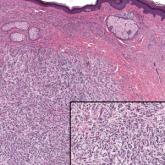

A 74-year-old man presented with an asymptomatic nodule on the left neck measuring approximately 2 cm. An excisional biopsy was obtained for...